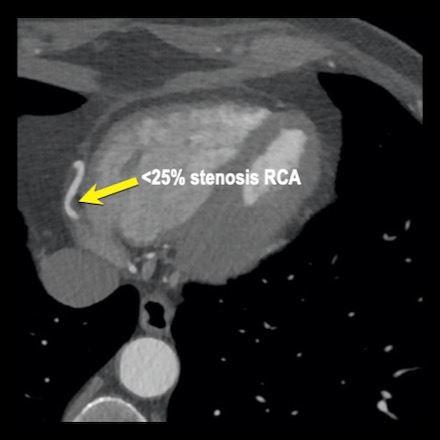

case 1 – CAD-RADS 2/P1

The findings are:

- Agatston score of

this patient was 14 (P1). Please, also note the calcification of the aortic valve. - Some partially

calcified and calcified plaques are present in the LAD with mild stenosis

(25-49%). - Calcified-plaque in

the LCX causing minimal stenosis (<25%). - Non-calcified

plaque in the distal RCA causing minimal stenosis (<25%). - This patient classifies

as CAD-RADS 2/P1, which means no further workup is needed.